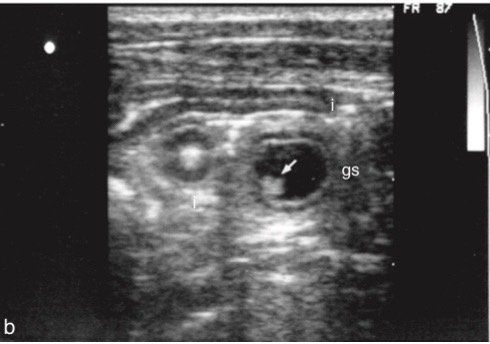

สำหรับโครงสร้างที่พบในขณะทำการตรวจอัลตร้าซาวน์ สามารถบ่งบอกอายุลูกสัตว์คร่าว ๆ ดังนี้